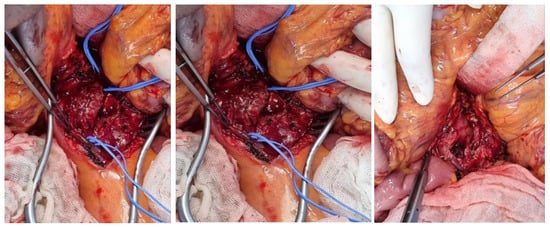

6.4. The Patient Was Diagnosed with SMA Aneurysm Using Abdominal CT, Which Was Followed by Persistent Abdominal Pain and Fever—Surgery Was Performed on the Transplanted Vessel